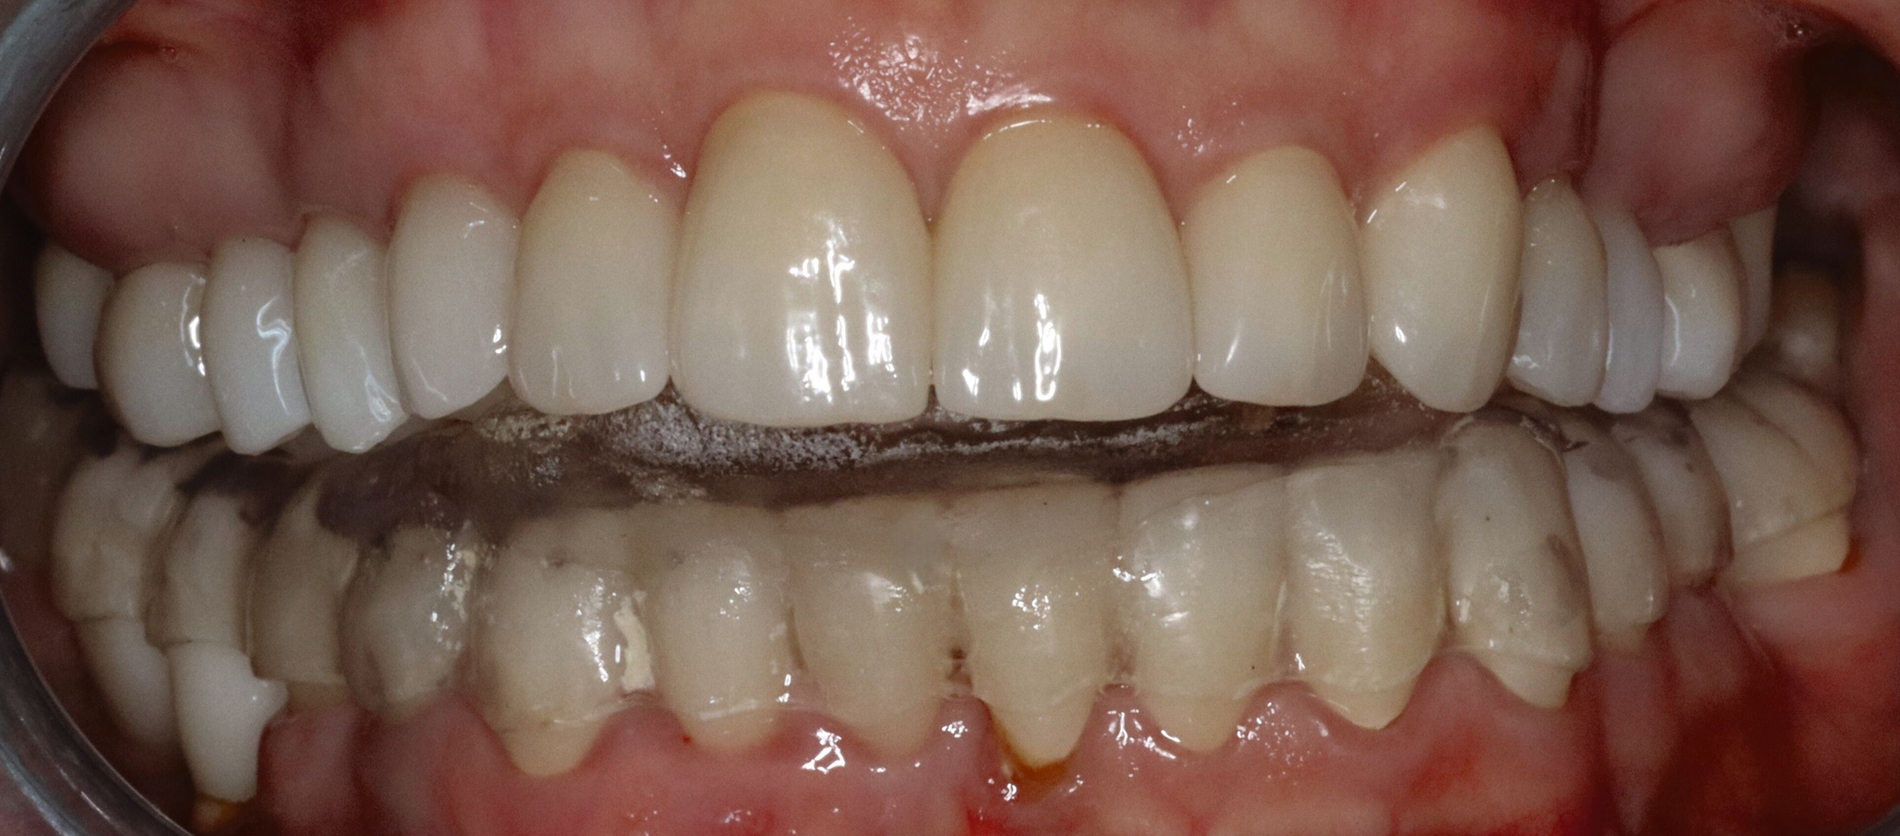

Mobilität des Unterkiefers eingeschränkt: Kieferöffnung aktiv ohne Schmerz 20 mm, aktiv mit myogenem Schmerz 32 mm, passiv 42 mm (Deflexion nach links, myogener Schmerz); unterdurchschnittliche Rechtslaterotrusion 4 mm und Linkslaterotrusion 6 mm (jeweils myogen schmerzhaft); Protrusion 4 mm (myogen schmerzhaft); Vertikaldimension unphysiologisch zu hoch (circa 2–3 mm) (Abbildungen 5 und 6).

Statische Vorkontakte 25/34 und 26/35 in geführter zentrischer Kondylenposition (entspricht dem subjektiven Erstkontakt) (Abbildungen 7 und 8) mit forcierbarem Gleiten in die maximale (Kronen)Interkuspidation circa 3 mm nach rechts (Abbildung 9).

Zahnärztliche und physiotherapeutische Therapie: Die Initialtherapie umfasste nach eingehender Aufklärung die Aufstellung eines Übungsplans mit Selbsthilfetechniken zur Muskelrelaxierung, eine schmerzreduzierende und relaxierende Medikation sowie die Fertigung einer Okklusionsschiene in therapeutischer Unterkieferposition ohne zusätzliche vertikale Sperrung, da im Kontaktbereich perforiert (Abbildung 10). Die Maßnahmen führten zu einer temporären Verbesserung der schmerzhaften Beschwerden. Weitergehend wird eine restaurative Neuversorgung mit Einstellung einer adäquaten vertikalen und horizontalen Kieferrelation erforderlich.